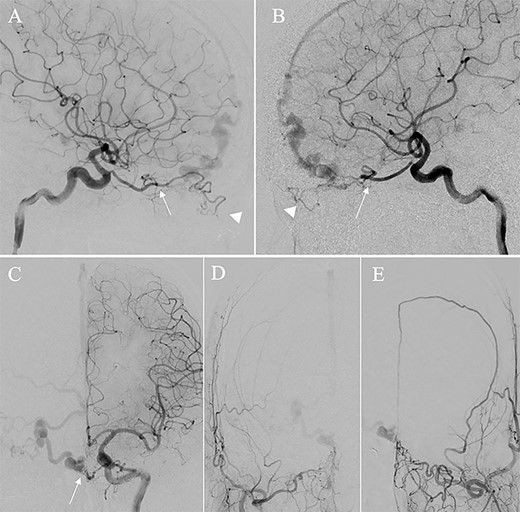

A patient in their 70s with extracranial lymphoma was incidentally found to have ACF–dAVF via head computed tomography and magnetic resonance angiography. Digital subtraction angiography (DSA) confirmed ACF–dAVF with multiple feeding branches, arising from bilateral OphAs, distal IMAs and the left middle meningeal artery (MMA), with cortical venous reflex (Borden type III, Cognard type IV) (Fig. 1). At the patient’s request, we chose endovascular, rather than surgical, treatment. We injected a 20% N-butyl-2-cyanoacrylate (NBCA)–lipiodol mixture into the fistula through bilateral ethmoidal arteries and the left MMA after we placed coils at the terminal branch of the right OphA. However, we could not achieve full penetration into the fistulous connections because of pressure secondary to high flow from the IMA branches, which resulted in incomplete obliteration (Fig. 1). Four months later, we repeated TAE by temporarily reducing nasal blood flow by inserting gauze infiltrated with xylocaine and epinephrine into the nasal cavities. After introducing the guiding catheter, an endonasal surgeon inserted X-ray-detectable surgical gauze infiltrated with 1% xylocaine and epinephrine (1:10 000) into bilateral nasal cavities using a nasal speculum, while paying full attention to avoid damage to the nasal mucosa. Then, we confirmed that the gauzes were placed in appropriate locations in the upper nasal cavity under fluoroscopic guidance. Immediately after insertion, we were able to confirm decreased blood flow from the IMA using DSA (Fig. 2). After this procedure, we navigated a DeFrictor Nano Catheter (Medico’s Hirata, Osaka, Japan) into the terminal branch of the OphA, which was connected to the dorsal nasal artery. Even though there was still a distance from the tip of the microcatheter to the shunt pouch, the NBCA reached the shunt point and penetrated the venous portion (Fig. 3). Follow-up DSA demonstrated complete obliteration of the ACF–dAVF, and blood flow in the nasal mucosa from the IMA branches recovered normally (Fig. 4).

Angiographic images, anteroposterior (A) and lateral (B) views, showing the microcatheter (arrow) navigated into the terminal branch of the left terminal branch of the ophthalmic artery, which connects to the dorsal nasal artery. Digital subtraction angiography, anteroposterior (C) and lateral (D) views, showing NBCA injected via the microcatheter (arrow) penetrating into the shunt point (arrowhead) without reflux of the NBCA. (E) Three-dimensional reconstruction of the skull showing the NBCA cast (arrow), which was embolized via the dorsal nasal artery.